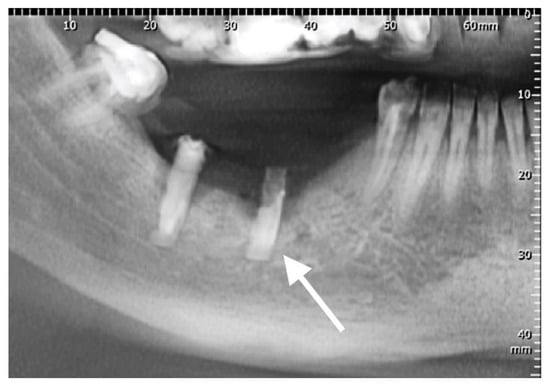

The third rejected implant (Sample 3) was recovered from position 4.5 of a 49-year-old woman, and is marked with an arrow on the dental radiography (Figure 4, arrow). Both implants in the lower right jaw were placed under local anesthesia in one session. After four years, the implants and the bridge reconstruction failed. The cervical segment of the implant was uncovered in the oral cavity. The patient reported pain in the areas of implantation, accompanied by mobility, gingival retraction, and inflammation. The interview and clinical examination revealed average oral hygiene, smoker status (20 cigarettes/day), and diabetes mellitus controlled by diet and prescription medication.

Figure 4. Radiography centered in quadrant 4 displaying incorrect positioning of inserted implants. Peri-implantitis with bone loss and exposure of the cervical segment of the implant are noted. The studied implant is marked with an arrow.